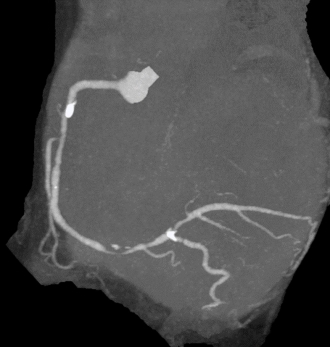

胸痛で来院された患者さん。右冠動脈に高度狭窄が疑われる